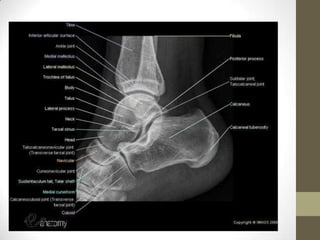

Lateral View of the Ankle

• The lateral surface of

the ankle is in contact

with the film, with the

foot slightly dorsiflexed.

Cross the opposite leg

over the leg being

examined, and support

the opposite knee to

avoid rotation of the

ankle.

Posterior tibial               Dome of the talus:

tuberosity fractures           centered under

& direction of fibular         and congruous

injuries can be                with tibial plafond

identified

Avulsion

fractures of

the talus by

the anterior

Any deformity                 capsule can

to the                        be identified

talus, calcaneu

s or subtalar

joint